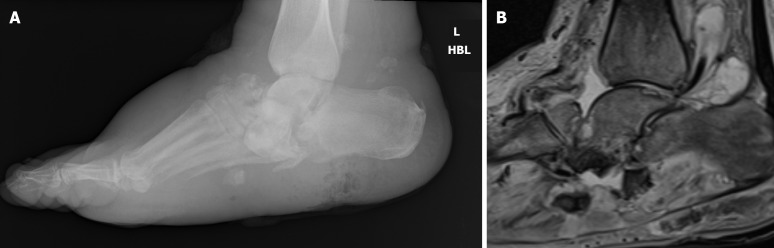

Abstract Image